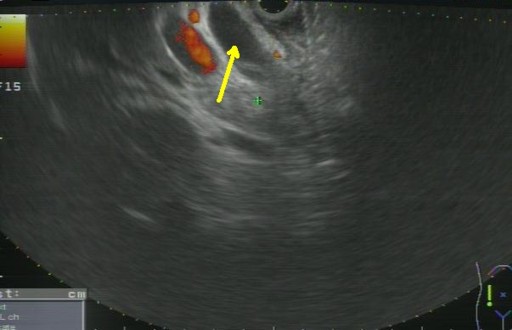

Thus, EUS-guided transduodenal biliary drainage (EUSBD) was performed. A linear array echoendoscope (GF-UCT140, Olympus America, Center Valley, PA, USA) was placed in the duodenal bulb allowing visualization of a dilated common bile duct (Figure 1). A 19-gauge FNA needle (Wilson-Cook Endoscopy, Winston-Salem, NC, USA) was used to perform a transduodenal puncture of the common bile duct through the proximal end of the duodenal stent. Bile was aspirated and a cholangiogram demonstrated good filling of the right and left duct systems with no evidence of a stricture proximal to the puncture site (Figure 2). Under fluoroscopy, a 0.035-inch straight guidewire (Jagwire, Boston Scientific Corporation, Natick, MA, USA) was passed into the biliary tree and directed toward the hilum. The FNA needle was exchanged for a biliary dilating balloon (Hurricane RX, Boston Scientific Corporation, Natick, MA, USA). The choledochoduodenostomy tract was dilated to 6 mm. A 10x60 mm fully covered self-expanding metal biliary stent (Wallfex®, Boston Scientific Corporation, Natick, MA, USA) was placed over the guidewire and deployed under fluoroscopy. One cm of the stent was left protruding into the duodenal bulb through the mesh at the proximal end of the duodenal stent (Figure 3). Good bile and contrast efflux was seen. The final fluoroscopic image did not demonstrate a bile leak (Figure 4). Post-procedure CT imaging demonstrated good positioning of the biliary stent and no evidence of a bile leak (Figure 5).

Figure 1. Linear EUS image from duodenal bulb demonstrating dilated common bile duct (yellow arrow). |